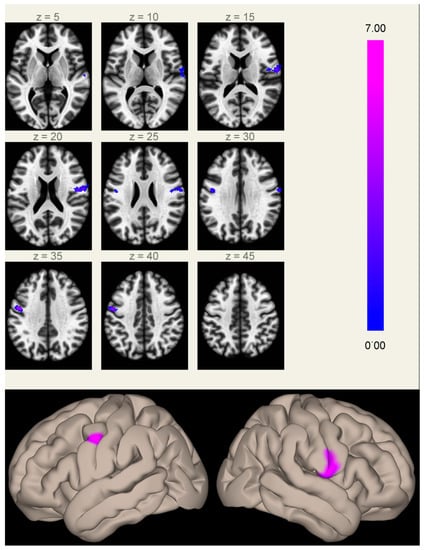

The processing speed, as measured at the d2-R test of attention, showed a significant inverse correlation, independent of the therapy group, with the FC of the MPFC seed in two symmetric clusters centered on the precentral gyri, substantially overlapping the same regions that showed significant differences in FC with the MPFC between the two groups (Figure 2).

Figure 2. Connectivity between the MPFC and the right (5.9 cm3, MNI coordinates [+50 +02 +26]) and left (2.3 cm3, MNI coordinates [−40 −08 +24]) rolandic opercular cortices (a region normally devoid of physiological correlation with the MPFC) correlated inversely with the speed of processing scores at the d2-R test, independent of the group membership. Clusters of significant inverse correlation are shown overlaid on the axial images from a standard T1-weighted volume in the MNI space (left, in neurological convention, MNI Z coordinates are reported for each slice), and projected onto its surface (right, upper panel). The color scale represents T-values from the GLM. In the lower right box, the processing speed scores (Y-axis) are plotted against the mean Fischer-normalized correlation coefficients of the significant clusters (X-axis) for both groups (Group A, filled marks; Group B, empty marks).